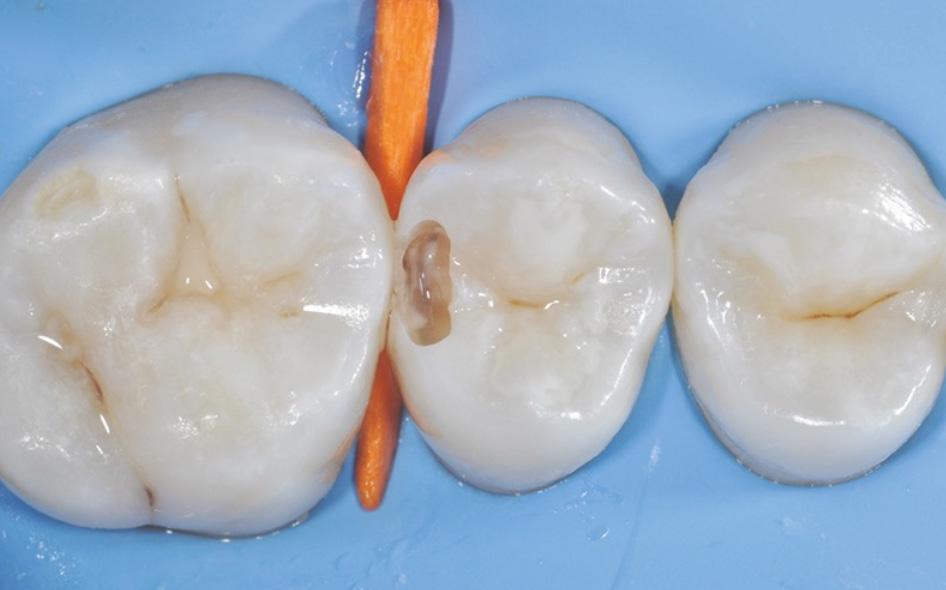

Fig. 5: Caries removal and cavity preparation. Caries detection dye was used as a Fig. 6: A 15 second selective enamel etch using 3M™ Scotchbond™ Universal Etchant followed by rinsing and air drying. Fig. 7: 3M™ Scotchbond™ Universal Adhesive was scrubbed into the preparation for 20 seconds followed by air-drying and light-curing with 3M™ Elipar™ LED Curing Light for 10 seconds.* Fig. 8: 3M™ Filtek™ One Bulk Fill Restorative A3 was placed in one increment. The composite was cured for 10 seconds on the occlusal surface.*